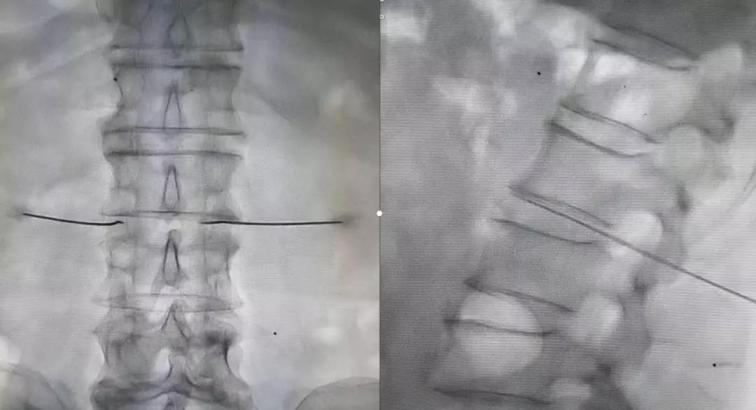

隨后制定了詳細(xì)的診療方案:1、進(jìn)一步完善相關(guān)檢查;2、每天早上給予骶管封閉、三氧血治療;3、實施腰交感神經(jīng)阻滯改善下肢血液循環(huán);4、待患者對初步治療效果認(rèn)可滿意后,給予腰交感神經(jīng)損毀治療,以此改善下肢血管痙攣性疼痛以及下肢血液供給狀況,給予保肢,達(dá)到治愈的目的。

診療方案雖然有了,但是要勸阻宋阿姨和家屬“截肢”的念頭還真是頗費周折。李巍安慰家人,按照醫(yī)生的方法治療3天,如果效果不好,我們再商量截肢的事情。家人半信半疑的答應(yīng)了。8月20日,經(jīng)過幾天的初步治療,宋阿姨和家人們明顯感覺到了患病小腿上的好轉(zhuǎn)變化。李巍又詳細(xì)向患者及家屬解釋了交感神經(jīng)阻滯及損毀能夠給疾病帶來的相關(guān)改善,并在征求病人及家屬同意后,給予患者腰交感神經(jīng)損毀治療。實施治療的第二天,宋阿姨下肢血管神經(jīng)性疼痛癥狀明顯緩解,下肢供血明顯改善,左下肢皮膚溫度較術(shù)前明顯提升,結(jié)痂周圍皮膚顏色也變得紅潤。